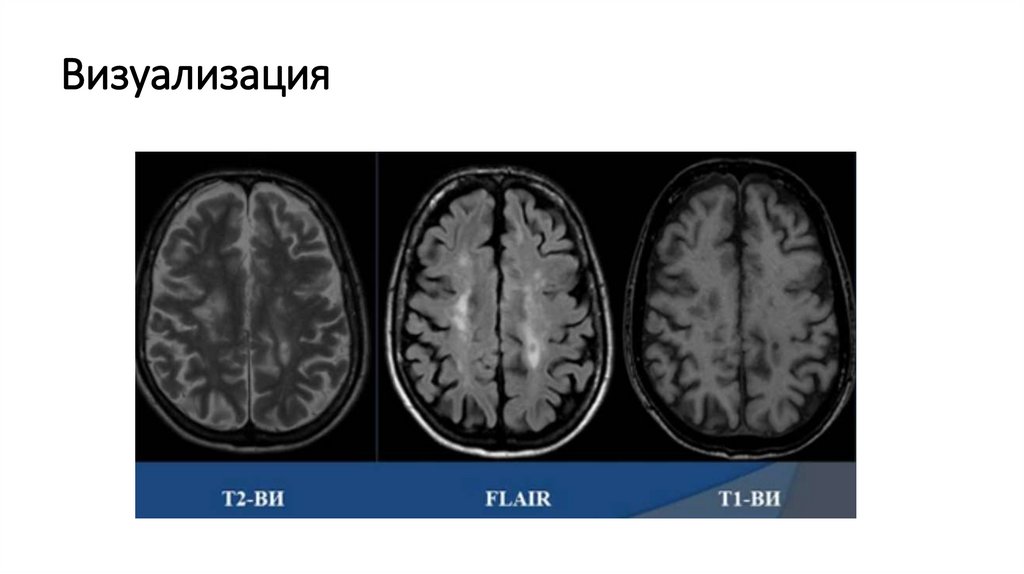

Методика исследования МРТ:

- Т2 ВИ в аксиальной и корональной проекциях

- последовательность с подавлением МР-сигнала от воды (FLAIR) в

саггитальной и аксиальной проекциях

- Т1 ВИ в аксиальной проекции до и после введения контраста

- DWI в аксиальной проекции

Бляшки рассеянного склероза гиперинтенсивны на Т2-ВИ, гипоинтенсивны на Т1-ВИ,

размерами от 3 мм и более, округлой или овоидной формы. Перивенулярное

(веноцентрическое) расположение бляшек РС подчеркивается многими исследователями.

Расположение очагов вдоль венул определяет их ориентацию перпендикулярно стенкам

боковых желудочков в виде «пальцев Доусона» на аксиальных и сагиттальных изображениях.